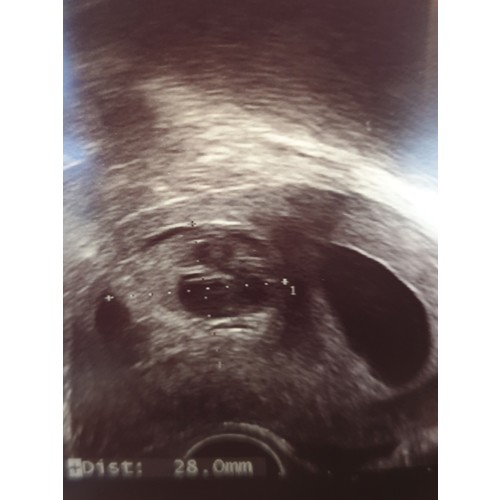

Ik had dit ook! Een grote bloedstolsel en los vocht/bloed in de baarmoeder. Flink bloedverlies helder en oud gedurende 2 weken en vruchtje bleef doorgroeien en hartje kloppen. Bij termijnecho was het helemaal schoon en inmiddels 14w zwanger van een klein wondertje.

Heb ik bij de eerste nooit gehad nu wel. Was ook erg bang dat het mis was. Maar verloskundige zei hier ook dat het nog wel even kon duren.(ook zo'n zwart plekje wat oud bloed was) Ook ik had soms rood bloed. Heeft 3 weken geduurd en is nu over.